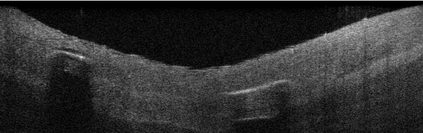

Coronary artery disease (CAD) is a cardiovascular condition with high morbidity and mortality. Intravascular optical coherence tomography (IVOCT) has been considered as an optimal imagining system for the diagnosis and treatment of CAD. Constrained by Nyquist theorem, dense sampling in IVOCT attains high resolving power to delineate cellular structures/ features. There is a trade-off between high spatial resolution and fast scanning rate for coronary imaging. In this paper, we propose a viable spectral-spatial acquisition method that down-scales the sampling process in both spectral and spatial domain while maintaining high quality in image reconstruction. The down-scaling schedule boosts data acquisition speed without any hardware modifications. Additionally, we propose a unified multi-scale reconstruction framework, namely Multiscale- Spectral-Spatial-Magnification Network (MSSMN), to resolve highly down-scaled (compressed) OCT images with flexible magnification factors. We incorporate the proposed methods into Spectral Domain OCT (SD-OCT) imaging of human coronary samples with clinical features such as stent and calcified lesions. Our experimental results demonstrate that spectral-spatial downscaled data can be better reconstructed than data that is downscaled solely in either spectral or spatial domain. Moreover, we observe better reconstruction performance using MSSMN than using existing reconstruction methods. Our acquisition method and multi-scale reconstruction framework, in combination, may allow faster SD-OCT inspection with high resolution during coronary intervention.